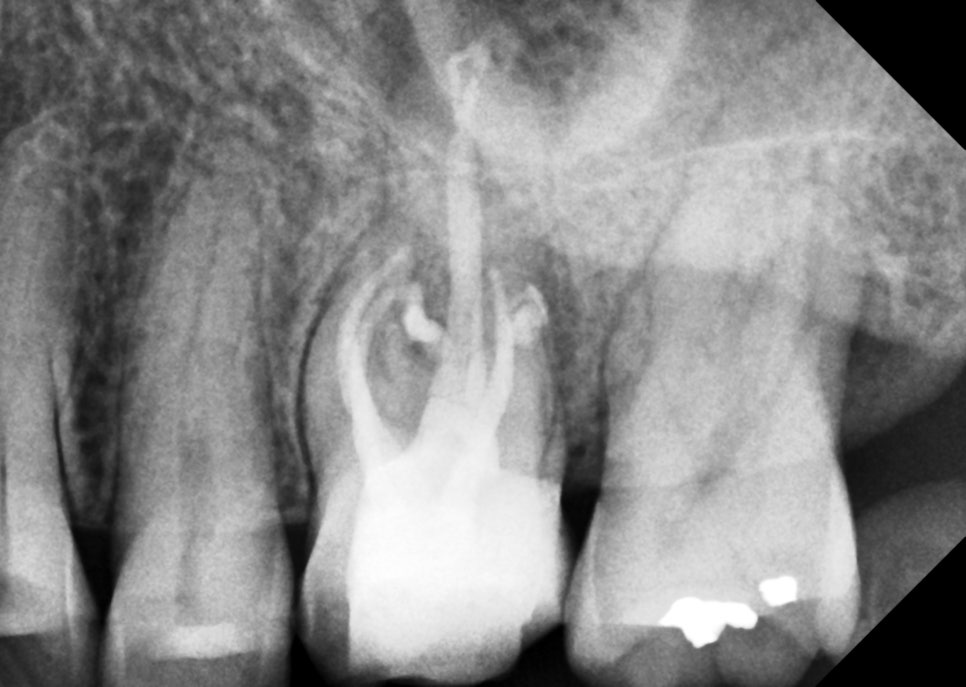

재신경치료 완료

동료들이 이거 보면 다들 고생했다고 할 것같다.

재신경치료라는 건 참 어렵다.

신경관 긁어내는 바늘이 부러지기도 쉽고

기존에 어설픈 시도로 인해서

시간이 지나며 신경관이 꽉 막혀버리기도 한다.

2차우식으로 인해서

남아나는 치아가 없어지기도 하고

염증을 일으키는 세균의 종류도

훨씬 강력한 놈이라

여러모로 어려운 치료이지만

그래도 할 수 있는 한 열심히 해봤다